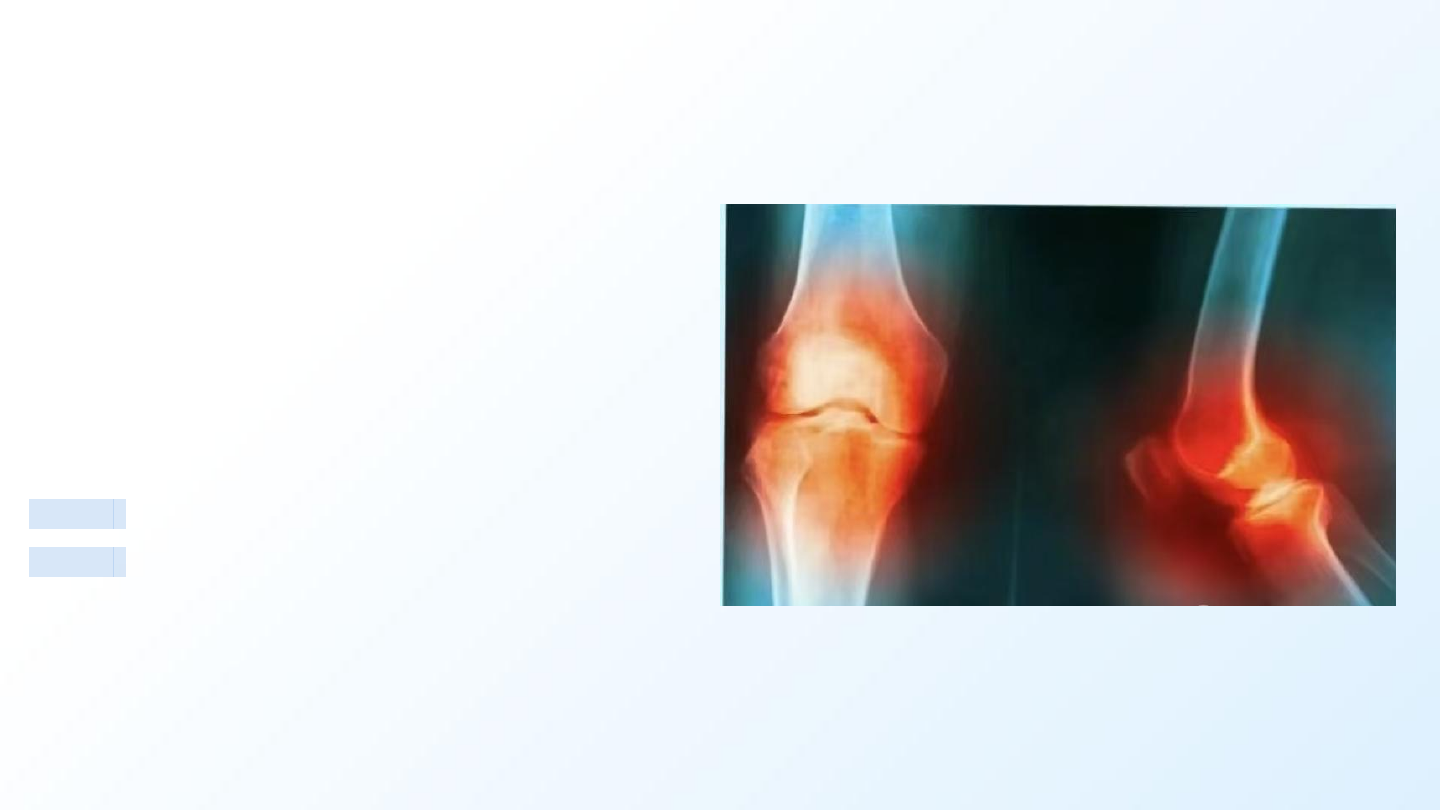

如何明确诊断?

诊断遵循“临床—影像—排除”三步法,X线检查是确诊的金标

准。

X光检查 (金标准)

观察 关节间隙变窄 、骨刺、骨硬化。